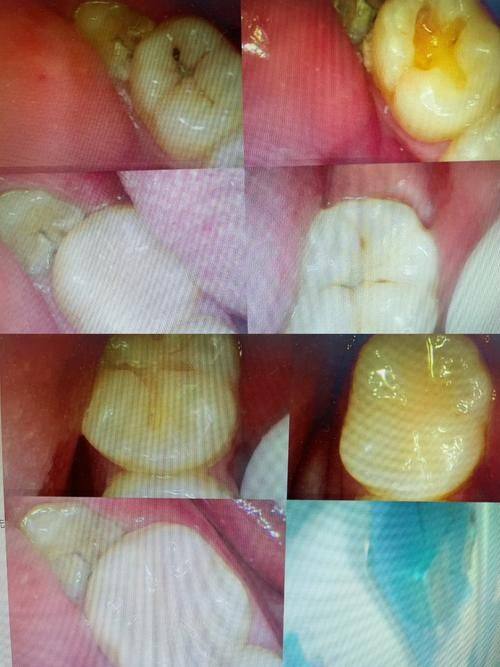

补牙是常见的口腔治疗手段,当牙齿出现龋洞等问题时,医生会将龋坏组织去除,然后用补牙材料填充。然而,不少患者在补牙后一段时间,会感觉牙齿又出现不适,从而担心补牙后内部会继续烂。这种疑惑并非空穴来风,因为在实际情况中,确实存在补牙后牙齿内部再次出现问题的现象。有些患者可能觉得自己补完牙就万事大吉了,却没想到后续还可能有状况发生。

在补牙过程中,如果牙齿没有杀神经,并且龋洞比较深,就可能为后续问题埋下隐患。补过的牙齿,虽然医生会把内部龋坏的部分清除干净,但牙本质小管会有渗透和反应。补牙之后,长期的咀嚼压力或者冷热食物的温度刺激,都可能激惹牙髓神经。就好像牙齿内部有一个“敏感区”,外界的刺激容易让它“发火”。深洞充填治疗一段时间后,牙齿可能会出现牙髓炎症状,内部开始继续发炎,这也就是特别多患者担心的补牙后内部会继续烂的一种情况。比如,患者在吃冷热食物时突然感到牙齿剧痛,这特别可能就是牙髓神经受到刺激的表现。

刷牙看似简单,但对于补过的牙齿来说,清洁不到位可是个大问题。补过的牙齿,牙齿和充填材料之间如果因为平时刷牙没刷干净,就会产生继发性龋齿。想象一下,牙齿和补牙材料之间就像有一个“小缝隙”,细菌容易在这里“安营扎寨”。随着时间的推移,这个“小缝隙”会逐渐出现小裂纹和缝隙,导致牙齿内部继续损坏。有些患者可能刷牙比较马虎,没有照顾到补过牙齿的各个角落,久而久之,就可能出现补牙后内部继续烂的情况。比如,可能会发现牙齿表面有小黑点,这可能就是继发性龋齿的早期表现。